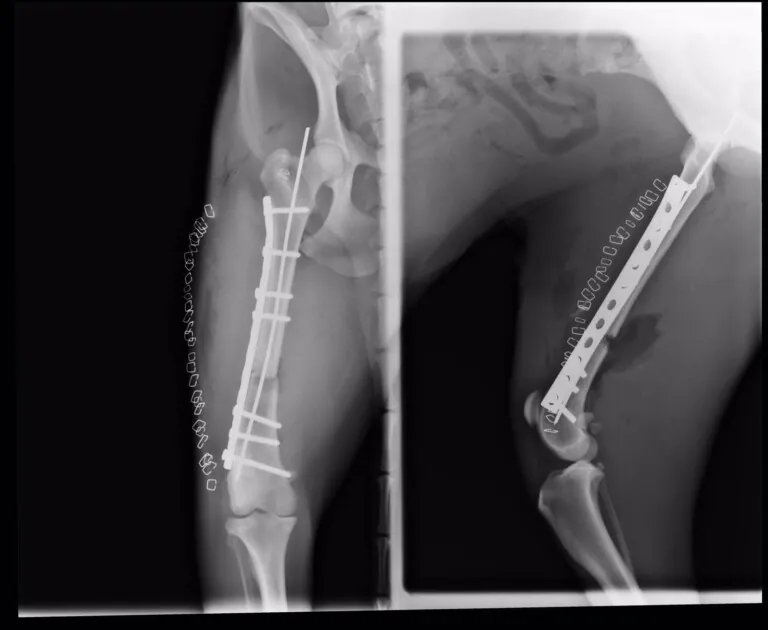

- Fracturas de huesos.

- Antes y después de una cirugía para ayudar al proceso de rehabilitación.